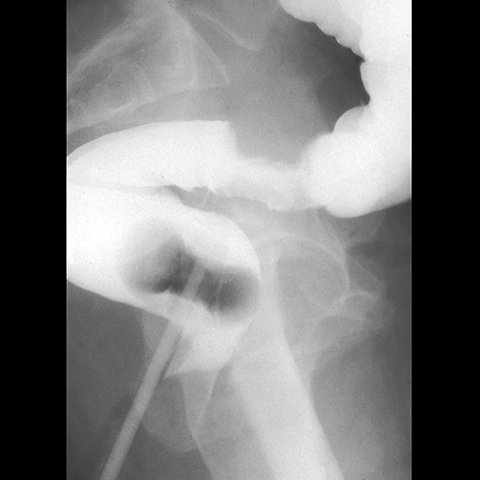

60 year-old male presents with hematochezia and weight loss. [2 of 2]